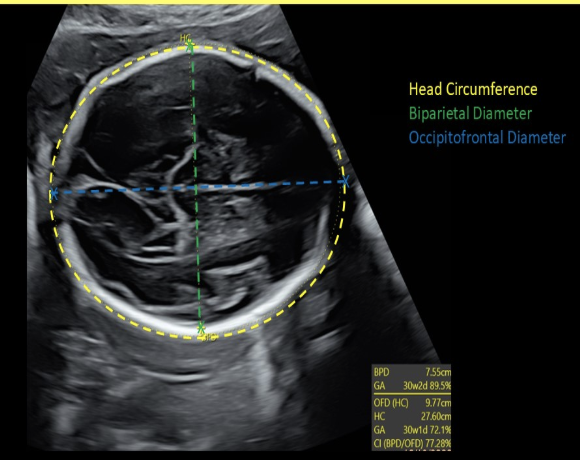

how to properly perform the occitpital-frontal (OFD) measurement of a fetus

.

a) coronal view of fetal head w/calipers placed from leading edge of the cranium

b) axial view of fetal head w/calipers placed from outer frontal edge to outer occipital edge of the cranium

c) axial view of fetal head w/calipers placed from the outer edge of one side of the cranium to the opposing outer edge of the cranium

d) axial view of fetal head w/calipers placed from side to side on outer edge of one side of the cranium to the opposing inner edge of the cranium

BPD measurements are taken from ____ edge of the skull to ___ edge of the skull

a) inner, inner

b) outer, inner

c) outer, outer

d) inner, outer

which biometric measurement is most accurate when predicting fetal age

a) AC

b) HC

c) BPD

d) FL

the correct cranial level for BPD + HC assessment is

a) Transverse axial view of the fetal skull at the level of the cavum septum pellucidum, third ventricle, and thalamus

b) Transverse axial view of the fetal skull at the level of the cerebellum and cisterna magna

c) Coronal view of the fetal skull at the level of the cavum septum pellucidum, third ventricle and thalamus

d) Transverse axial view of the fetal skull at the level of the lateral ventricles and choroid plexus